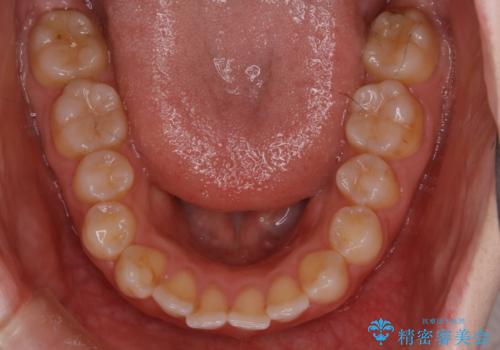

【非抜歯】上下の前歯が噛み合わないオープンバイトの治療

- 噛み合わせの不調を主訴にご来院されました。

骨格的な問題もあり、噛んだ時に奥歯しか当たらず前歯の被蓋があまりない状態でした。

奥歯を沈めて噛み込みを深くしていくことで被害の改善が起こるとともに、下顎自体が前上方に回転移動することで顔貌的にも変化を出すことができます。

臼歯の位置が高く噛んだ時に奥歯しか当たらなかったり、舌癖などが原因で前歯が前に倒れてしまうことで上下の前歯の被蓋がなくなってしまっている状態をオープンバイトといいます。

前者の場合は臼歯を圧下し沈めてあげることで改善させます。後者の場合は前方に傾斜している歯を元の角度に戻してあげることで改善しますが、舌癖がある場合はその癖自体を無くす治療をしない限りまた同じ状態へと後戻りしてしまいます。